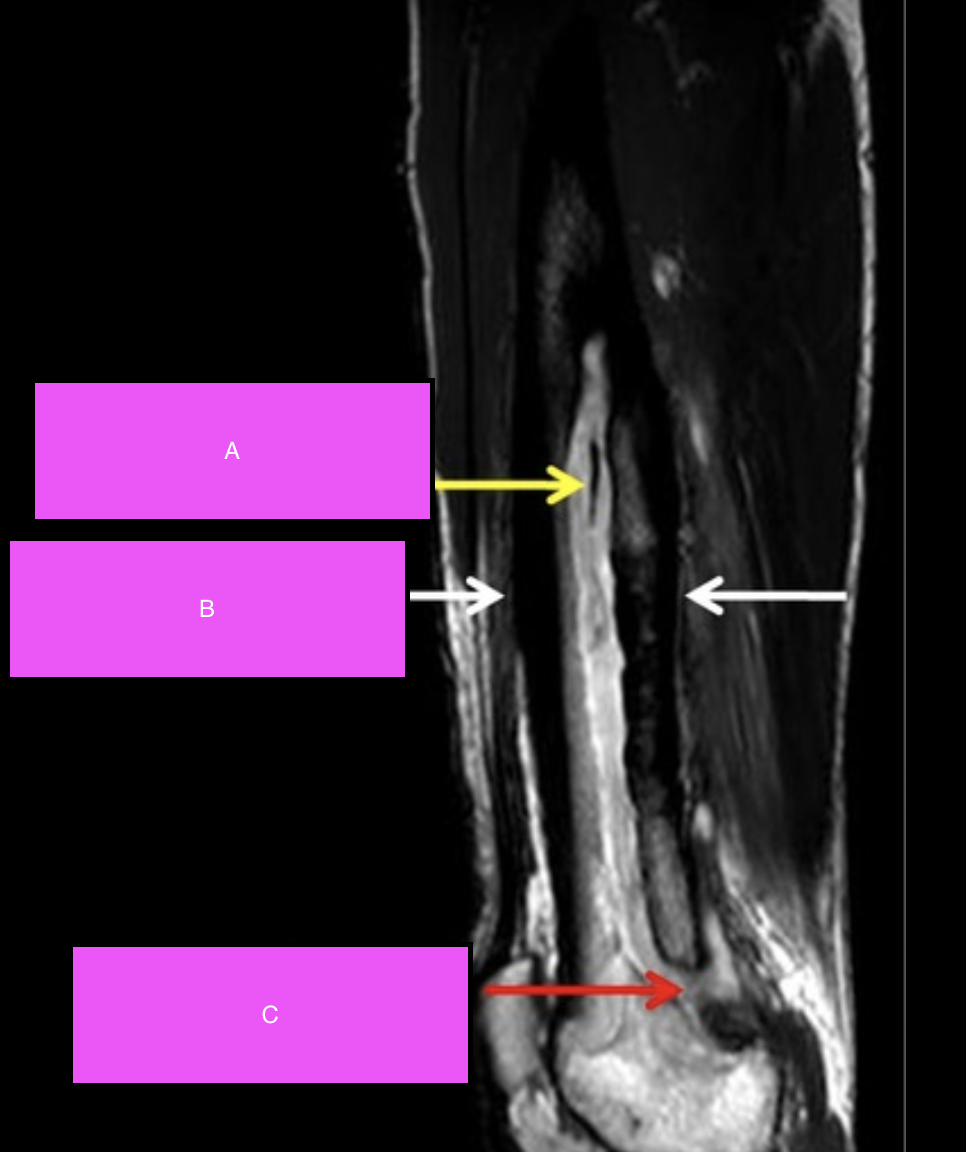

Q

Label A-C

A

Sequestrum: Refers to a dead piece of devitalised bone that has been separated (i.e. sequestered) due to necrosis from the surrounding bone.

Involucrum: New growth of periosteal bone around a sequestrum.

Cloaca: An opening in an involuvcrum that allows the internal necrotic bone and pus to discharge out.